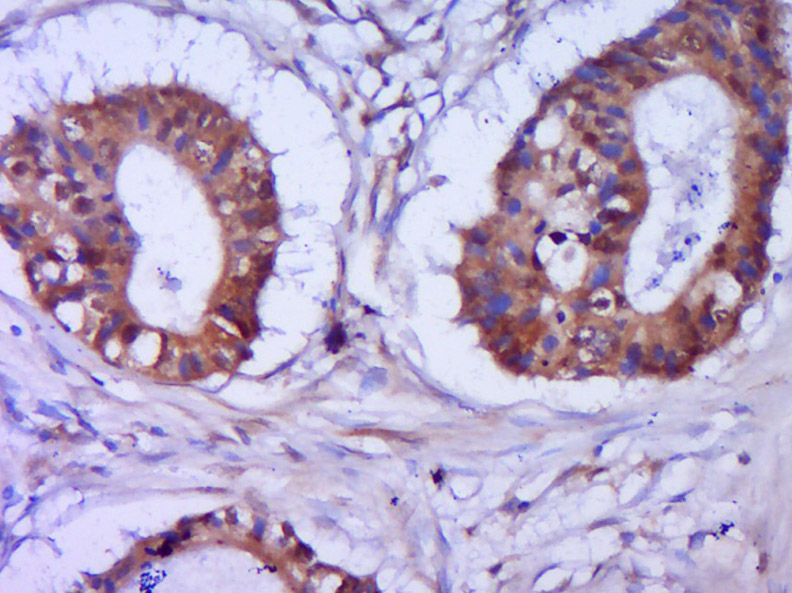

產(chǎn)品圖片

Paraformaldehyde-fixed, paraffin embedded (Human cervical cancer); Antigen retrieval by boiling in sodium citrate buffer (pH6.0) for 15min; Block endogenous peroxidase by 3% hydrogen peroxide for 20 minutes; Blocking buffer (normal goat serum) at 37°C for 30min; Antibody incubation with (p-CDKN1A (Ser146)) Polyclonal Antibody, Unconjugated (bs-5239R) at 1:400 overnight at 4°C, followed by operating according to SP Kit(Rabbit) (sp-0023) instructionsand DAB staining.